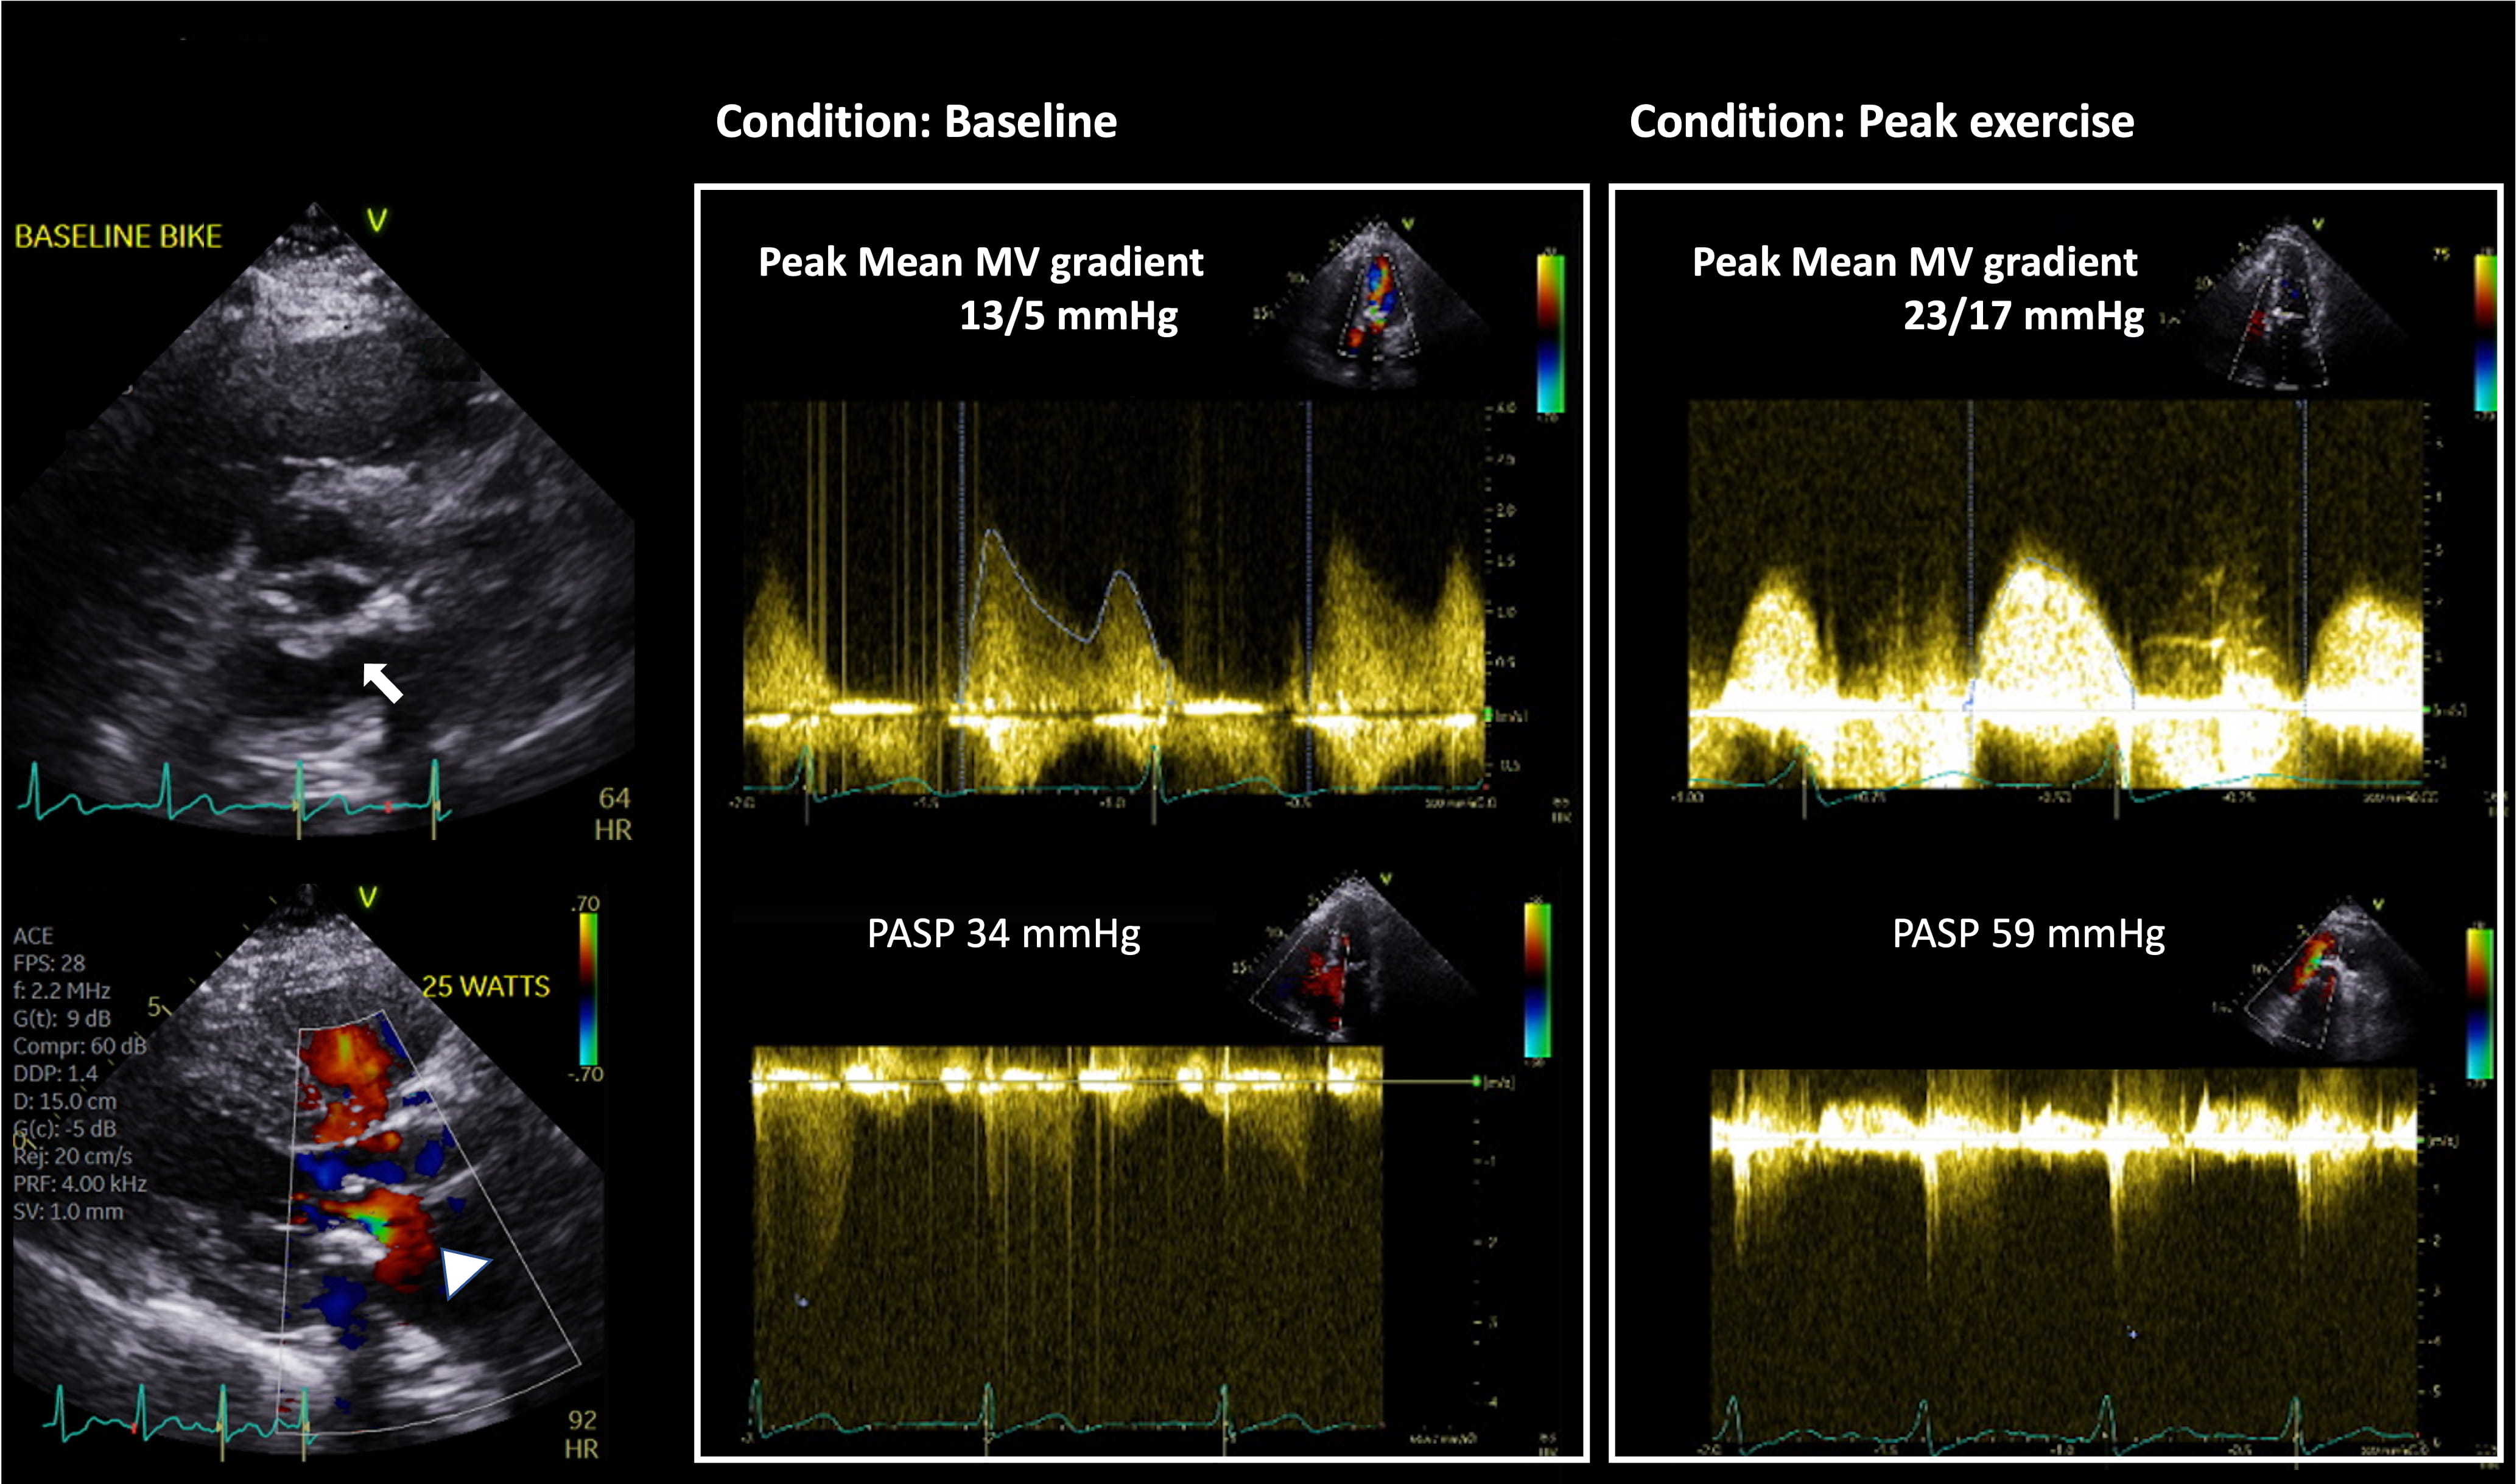

Fig. 2.Utility of Supine Bike Stress Echocardiography in assessment of

DMS. This is an 80-year-old woman with a prior history of coronary artery disease

who underwent coronary artery bypass graft surgery and surgical aortic valve

replacement with 21 mm Medtronic Mosaic valve 4 years prior. She presented with

progressive dyspnea on exertion. Her aortic valve prosthesis showed normal

function with pressure gradients unchanged from prior. Of note, severe mitral

annular calcification with posterior MV leaflet restriction (arrow) and flow

acceleration across the MV in diastole (arrowhead) are seen. MVACEQ is 1.5

cm